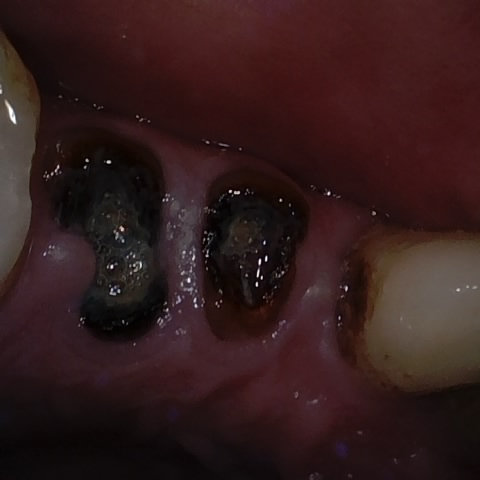

Annotated as "Good"